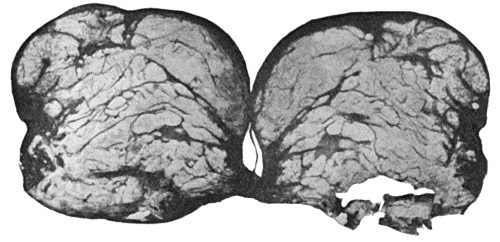

118.Shaft of the Femur after Acute Osteomyelitis 444

119.Femur and Tibia showing results of Acute Osteomyelitis 445